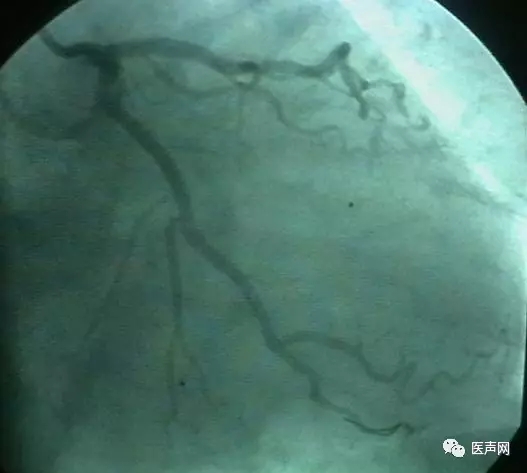

病例6:小血管病变处理---药物涂层球囊+金属裸支架(DCB+BMS)

中间支PCI术后,复查CAG,无ISR。RCA远端90%狭窄,小血管病变,中段40%狭窄 处理:小血管病变处理策略---药物涂层球囊+金属裸支架(DCB+BMS)(附图)

DCB(Eurocro, DIOR):2.5×15@8-10bar,2min

BMS(Motion): 2.5×18@14bar,20sec

药物涂层球囊扩张

支架术后

这是余江涛教授刚刚开始做的新课题,用DCB治疗小血管病变(small vessel lesion)。